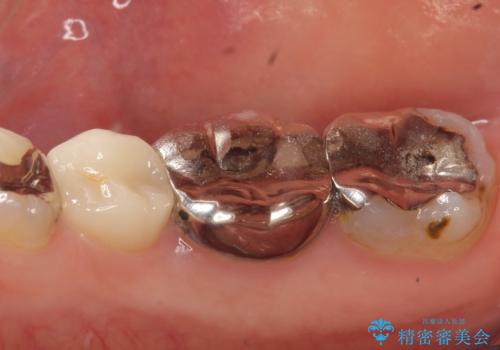

- 右下の奥歯でものを咬むと違和感があるので診て欲しいといらっしゃった方の症例です。

右下6は神経が死んでいたため根管治療を行い、オールセラミッククラウンによる補綴を行いました。

右下7は冷たいものがしみていたため、銀歯を除去後、オールセラミッククラウンによる補綴を行いました。